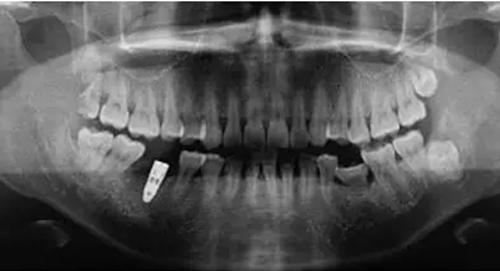

制作放射模板;制備PRF(圖2);微創(chuàng)拔除46后植入PRF(圖3)。3個(gè)月后CBCT分析骨質(zhì);行46種植牙修復(fù)術(shù)(圖4)。種植術(shù)后曲面體層片見圖5。病例2應(yīng)用骨粉膠原塞牙槽位點(diǎn)保存后一例基本情況患者男性,47歲。主訴:右下后牙折裂半月。

圖4 種植術(shù)中(A.種植術(shù)中切開翻瓣后所示骨面情況;B~E所示為種植術(shù)中環(huán)型鉆取骨情況;F所示為種植體植入縫合后)

圖5 種植術(shù)后曲面體層片